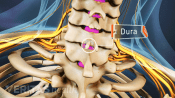

Injections relieve neck and back pain by delivering medications directly to the affected area, reducing inflammation.